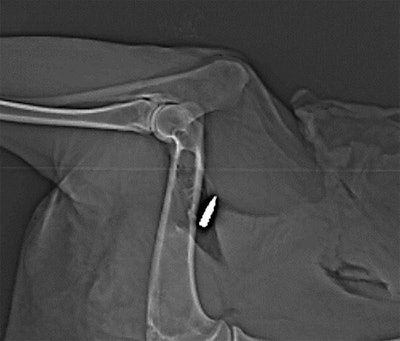

Gascho and colleagues thus set out to test the viability of using DECT to examine various kinds of bullets embedded in an animal cadaver: eight steel-jacketed lead bullets, four brass-jacketed lead bullets, and four solid bullets consisting of a copper-zinc alloy. Only the steel-jacketed bullets were ferromagnetic (American Journal of Roentgenology, September 2019, Vol. 213:3, pp. W105-W113).

They used various combinations of tube voltages to scan the bullets multiple times with DECT; the bullets were positioned both near and far from bone and in two different directional orientations. Next, they applied the extended CT scale algorithm to the imaging data to obtain more detailed image reconstructions of the bullets. Finally, they calculated the dual-energy index of the bullets using three different voltage pairs: 80 kVp and 140 kVp, 100 kVp and 140 kVp, and 120 kVp and 140 kVp.

After analyzing the data, the researchers found that DECT was able to discern differences between the lead bullets and copper-zinc bullets, regardless of the type of jacket surrounding the bullet. The copper-zinc bullets had higher average and peak dual-energy indexes than the lead bullets by a statistically significant degree (p < 0.01). Gascho and colleagues determined that the best dual-energy pair to distinguish the different types of bullets was 120 kVp and 140 kVp.